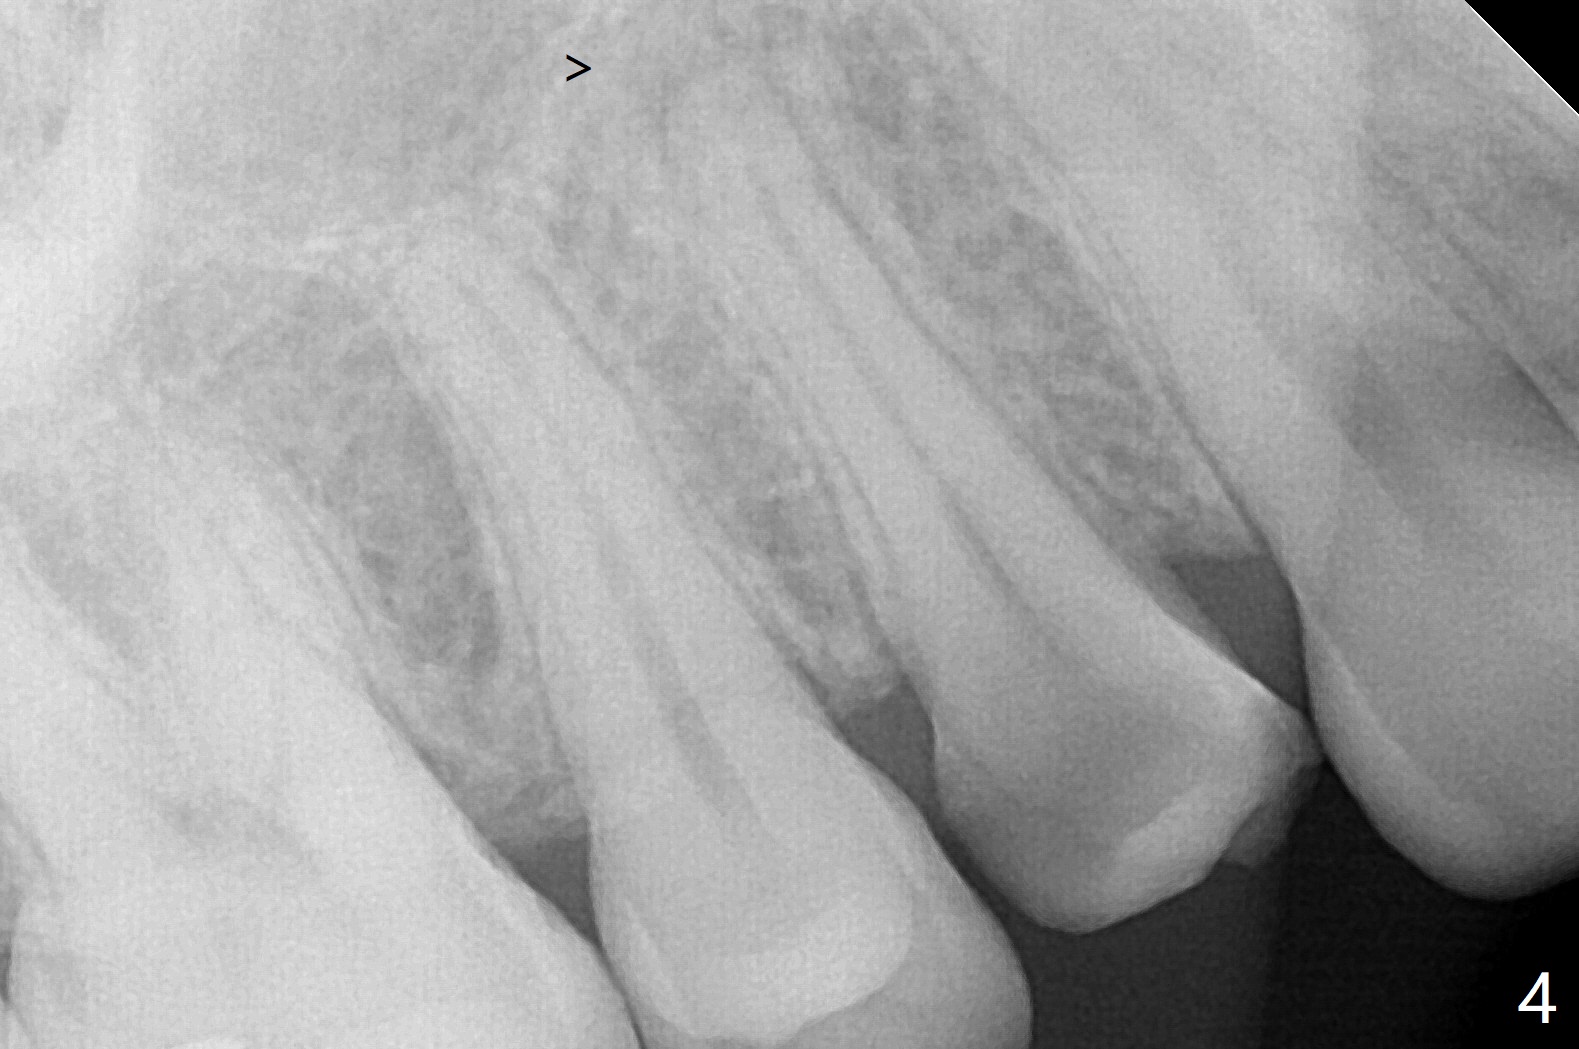

今天临床实践让我对植骨概念和操作有两方面突破,与大家分享讨论。PRF/sticky bone(粘性骨粉)以及血小板因子(成品)对软硬组织缺损修复重建无疑起到不可缺少作用。但是大多数拔牙病例并不是那么严重,放置骨粉和覆盖胶原膜足够了。为了避免费时的缝线固定胶原膜,介绍一种简易固定方法,助手可以做。31岁女不想保留严重龋坏右上4(图一至四,拍摄临床照片,与后期比较,但愿简易植骨不产生骨板塌陷),虽然术前根尖片显示根尖阴影(图四),术中没有根尖骨板缺失。估计没有严重骨板缺损,她又年轻,再生能力强,所以做简易植骨(异体骨,图五),也就是不需要PRF或者血小板因子,骨粉表面放置GEM CAP(9-12月吸收膜),由胶水固定(图六),在放置牙周敷料前,在胶原膜表面涂一层含有抗单纯疱疹病毒凡士林(图七),但愿敷料脱落时,不至于把胶原膜带下来。术后第六天,病人由于左上第二磨牙不适回来,说敷料脱落,没有不适,要求检查,其实膜也丢失(图八,九),骨粉好像挺稳定,没有做如何处理,尽管少量骨粉离开牙槽窝(<)。